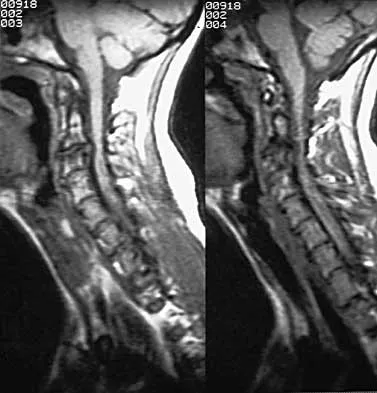

Question 33High Yield

A 40-year-old carpenter has a 3-month history of right arm pain and neck pain that now leaves him unable to work. Examination reveals a positive Spurling test, weakness of the biceps, and a mildly positive Hoffman's sign on the right side. Electromyography and nerve conduction velocity studies show a right C6 deficit. Figures 27a through 27c show MRI scans that reveal two-level spondylotic disease at C5-6 and C6-7, a large herniated nucleus pulposus at C5-6, and a prominent ridge and hard disk at C6-7. Nonsurgical management fails to provide relief, so the patient elects surgical intervention. Which of the following surgical options would give the best long-term results?

Explanation